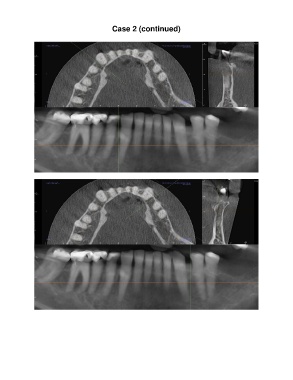

Case 2 (continued)